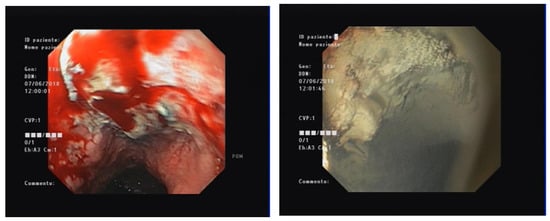

4.2. Is HP a Possible Gold Standard in Malignancy-Related NVUGIB?